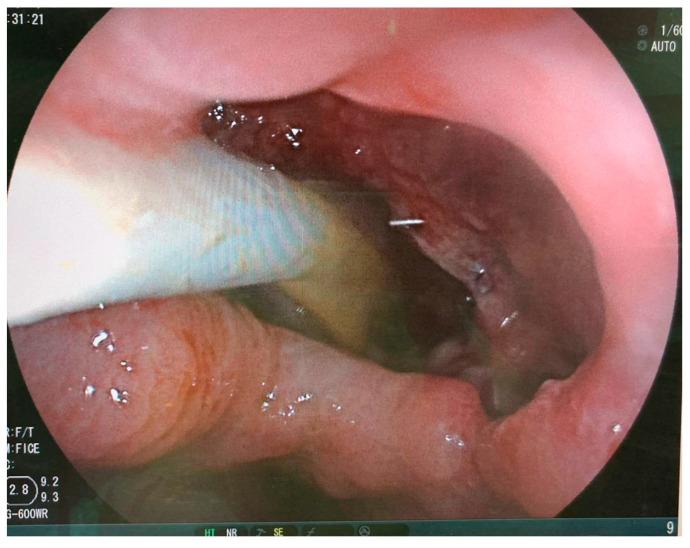

Post-sleeve gastrectomy fistulas are a rare but possibly severe life-threatening complication. Besides early reoperation and drainage, endoscopy is the main treatment option. According to the clinical setting, endoscopic treatment options comprise stent or clip placement. New endoscopic therapies have recently gained attention, including endoscopic vacuum therapy, VacStent therapy, endoscopic internal drainage with pigtail stents, endoscopic suturing and stem cell injection. In this narrative review, we shed light on recent literature, developments, indications and contraindications of these treatments. Intragastric gastric band migration is a rare complication after gastric band positioning. Reoperation can sometimes be difficult, especially when a gastric band has already migrated far into the stomach. Endoscopic retrieval can be a valid, non-invasive therapeutic solution. We reviewed the current literature on this matter.

袖状胃切除术后瘘是一种罕见但可能严重危及生命的并发症。除了早期再次手术和引流外,内镜检查是主要的治疗选择。根据临床情况,内镜治疗方法包括放置支架或夹子。最近,新的内镜治疗方法受到关注,包括内镜下负压治疗、VacStent治疗、猪尾支架内镜内引流、内镜缝合和干细胞注射。在这篇叙述性综述中,我们阐明了这些治疗方法的最新文献、进展、适应证和禁忌证。胃内胃束带移位是胃束带放置术后的一种罕见并发症。再次手术有时可能很困难,尤其是当胃束带已经深入胃内时。内镜取出可能是一种有效的非侵入性治疗解决方案。我们回顾了关于此事的当前文献。